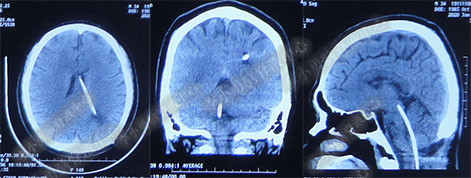

术后7天(2016年5月18日),症状有所缓解,复查头部MRI(图-2)幕上脑室较术前缩小,但是“四脑室仍扩张”,医生认为 “正常”于术后8天(2016年5月19日)出院。

图-2:2016年5月18日头部MRI